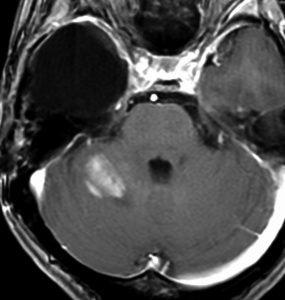

その2年後の画像です。右小脳半球に再発しています。右側頭葉腫瘍との連続性は全くありませんでした。脳幹部にも腫瘍はありません。遠隔再発 remote recurrenceというもので,星細胞系腫瘍 astroytic tumor AAやGBMではよく知られている現象です。乏突起膠細胞系腫瘍でもまれにみられます。